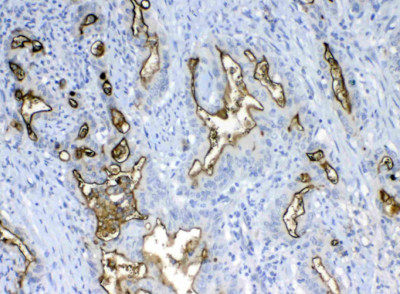

IHC (Immunohistochemistry)

(Figure 5. IHC analysis of MUC1 using anti-MUC1 antibody (AAA124555).MUC1 was detected in paraffin-embedded section of human mammary cancer tissue. Heat mediated antigen retrieval was performed in citrate buffer (pH6, epitope retrieval solution) for 20 mins. The tissue section was blocked with 10% goat serum. The tissue section was then incubated with 1ug/ml rabbit anti-MUC1 Antibody (AAA124555) overnight at 4 degree C. Biotinylated goat anti-rabbit IgG was used as secondary antibody and incubated for 30 minutes at 37 degree C. The tissue section was developed using Strepavidin-Biotin-Complex (SABC) with DAB as the chromogen.)